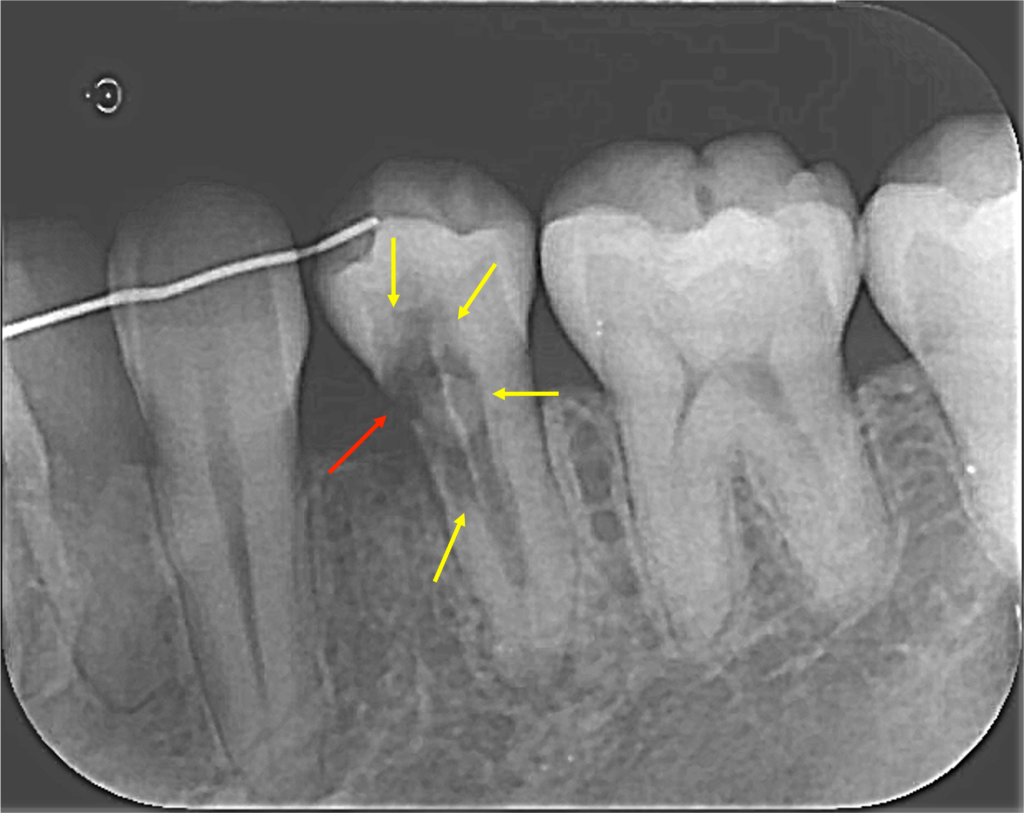

矯正の先生からは、内部吸収をしているので治してほしいと言われてたのですが、レントゲンを撮って良く見てみるとこれは外部吸収でした。

外部吸収も同様に虫歯ではなく、破歯細胞が歯の外側から歯を溶かしていき歯の内部に吸収が侵攻する病気です。

上のレントゲンを見ていただくとわかると思いますが、赤矢印の先(歯の外側から)吸収が開始され、歯の内部に吸収が向かい黄色矢印のところまで歯の内部が溶けてしまっているのです。

この病名は、ICR(Invasive Cervical Resorption)「侵襲性歯頸部外部吸収」(しんしゅうせいしけいぶがいぶきゅうしゅう)といいまして、